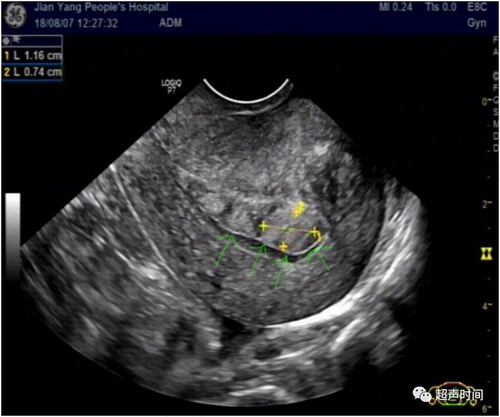

子宫内膜息肉在利用超声检测时候的表现,其声像图也可表现为不典型而呈低回声或者是一种杂乱回声,并且当子宫内膜息肉中间囊性发生变性时,其内在可见到液性小暗区。而子宫内膜较厚时,其内膜形态回声欠均匀或并不对称。这些都为子宫内膜息肉超声表现的基本形式。